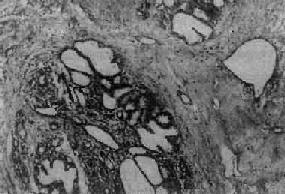

图13-24 纤维腺病

末梢导管、腺泡和间质均呈明显增生,部分腺泡及导管扩张,间质内有一些淋巴细胞浸润